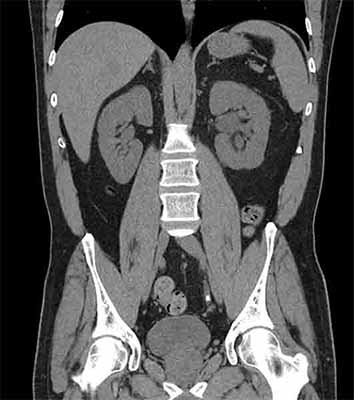

Left-sided Abdominal Pain in a 45-yr-old Man

Test Result 2

CT scans without contrast of the abdomen and pelvis are obtained and are shown.

Select each image to review.